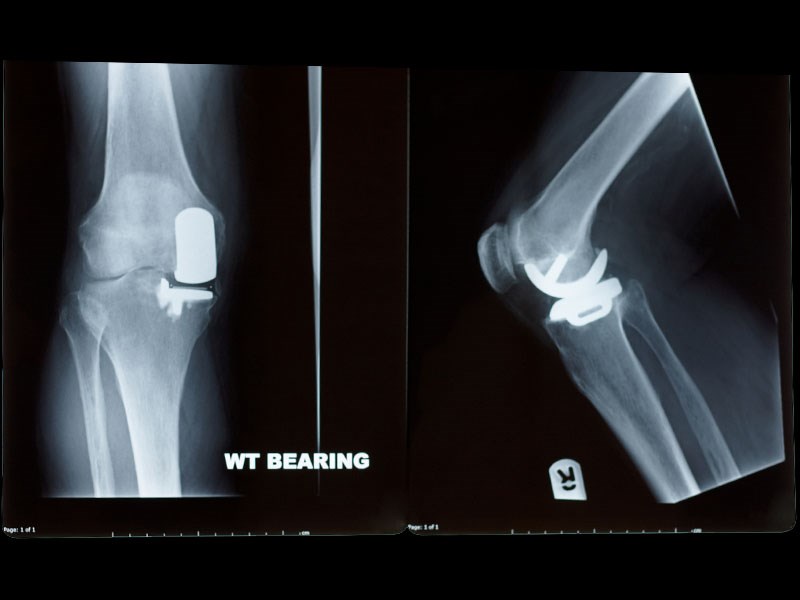

A half or partial knee replacement is a major operation that involves replacing one half of your knee joint with an artificial joint, normally the inside half.